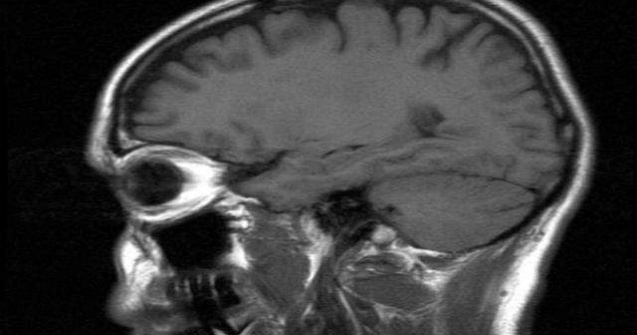

Pilotii care zboara adeseori la altitudini mari prezinta un risc crescut de leziuni cerebrale, afirma autorii unui studiu publicat luni in revista americana Neurology.